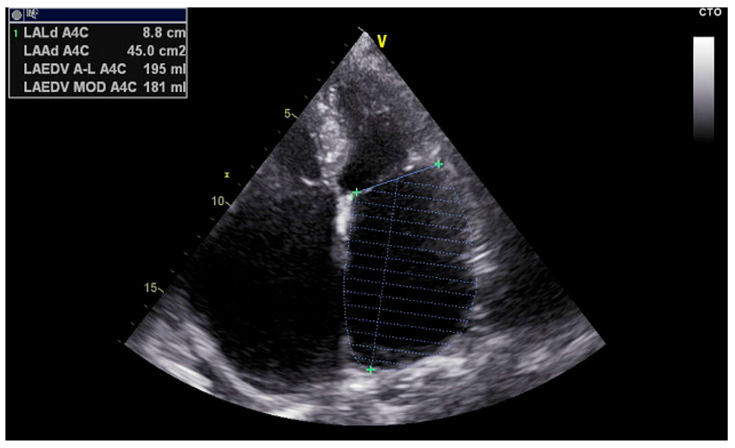

背景:阵发性心房颤动(PAF)是一种常见的心律失常,常采用导管消融治疗,尤其是肺静脉隔离(PVI)。然而,复发仍然很频繁,并且通常与未被识别的左心房结构和功能重塑有关。方法:我们引入超声心动图心房应变和传导评估(EASE)评分作为一种理论的、无创的模型,对导管消融治疗PAF患者的复发风险进行分层。该评分基于综合超声心动图参数能够反映与消融结果相关的心房重构程度的假设。结果:EASE评分结合了六项超声心动图指标——左心房储层应变(LASr)、心房传导时间(PA-TDI)、左心房容积指数(LAVI)、刚度指数(E/ E′/LASr)、E/ E′比和收缩应变(LASct)——每项指标都代表了结构、电或机械重构。总分从0到12分,将患者分为心律失常复发的低、中、高风险三类。初步回顾性数据显示,较高的EASE评分与消融后复发率增加之间存在显著关联。结论:EASE评分为PAF消融的无创风险预测提供了生物学上合理的多维框架。有必要进行前瞻性研究以验证其临床应用并完善其结构。

Background: Paroxysmal atrial fibrillation (PAF) is a common arrhythmia often treated with catheter ablation, particularly pulmonary vein isolation (PVI). However, recurrence remains frequent and is often linked to unrecognized structural and functional remodeling of the left atrium. Methods: We introduce the Echocardiographic Atrial Strain and conduction Evaluation (EASE) score as a theoretical, noninvasive model to stratify recurrence risk in patients undergoing catheter ablation for PAF. The score is based on the hypothesis that integrated echocardiographic parameters can reflect the extent of atrial remodeling relevant to ablation outcomes. Results: The EASE score combines six echocardiographic metrics-left atrial reservoir strain (LASr), atrial conduction time (PA-TDI), left atrial volume index (LAVI), stiffness index (E/e'/LASr), E/e' ratio, and contractile strain (LASct)-each representing structural, electrical, or mechanical remodeling. The total score ranges from 0 to 12, stratifying patients into low, intermediate, and high-risk categories for arrhythmia recurrence. Preliminary retrospective data suggest a significant association between higher EASE scores and increased recurrence rates following ablation. Conclusions: The EASE score offers a biologically plausible, multidimensional framework for noninvasive risk prediction in PAF ablation. Prospective studies are warranted to validate its clinical utility and refine its structure.